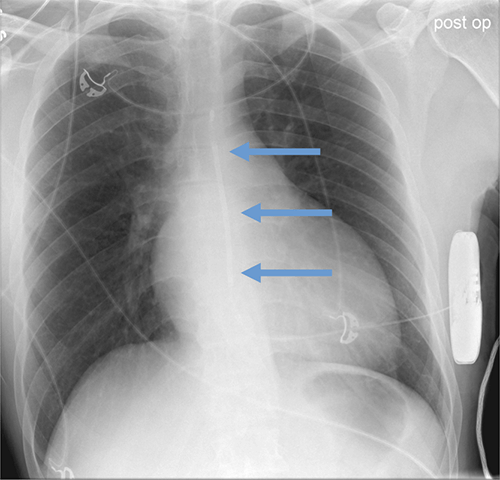

- CEID images with lead types:

Pacemaker with transvenous leads

Pacemaker with epicardial leads

Defibrillator lead

Subcutaneous defibrillator

Cut epicardial wires (often hard to see)

Abandoned leads

Abanded leads plus generator

Temporary transvenous lead

Leadless pacemaker